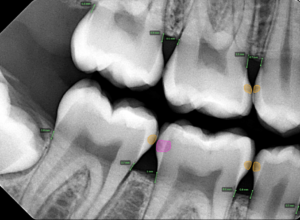

- Digital Radiographs